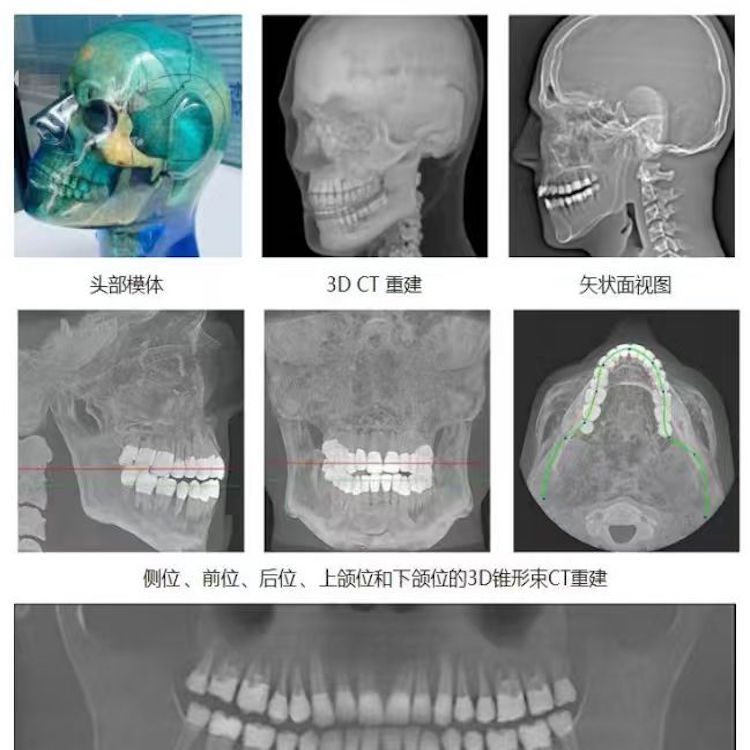

頭部模體是頭部診斷放射學(xué)的參考標(biāo)準(zhǔn),該模體旨在協(xié)助技術(shù)和臨床人員,在大多數(shù)需要精細(xì)解剖細(xì)節(jié)的放射學(xué)程序中選擇、監(jiān)測(cè)、培訓(xùn)和驗(yàn)證掃描參數(shù)。 模體為研究人員、臨床醫(yī)生和技術(shù)人員提供了一致性的工具。它非常適合確定最佳系統(tǒng)設(shè)置、調(diào)試新設(shè)備、監(jiān)測(cè)系統(tǒng)性能和培訓(xùn)牙科X射線、全景X射線、CT和錐束CT程序。 這個(gè)模體包括一個(gè)可調(diào)節(jié)的支架,用于在錐束 CT 或全景X射線系統(tǒng)中定位。模體的下頜略微張開(kāi),前牙垂直排列,以復(fù)制正確的咬合引導(dǎo)定位 。 請(qǐng)注意,實(shí)際咬合引導(dǎo)無(wú)法在這個(gè)產(chǎn)品中定位。 頭部模體是由專有組織等效材料制成的。由組織模擬樹(shù)脂制成,這些樹(shù)脂模擬X射線對(duì)人體的衰減特性,適用于CT和治療能量范圍(50keV-25MeV)。 模體在大小和結(jié)構(gòu)上都近似于平均男性頭部 。該模體包括詳細(xì)的3D擬人化解剖結(jié)構(gòu), 包括大腦、骨骼、喉、氣管、鼻竇、鼻腔和牙齒。骨骼包括皮質(zhì)和骨小梁的分離。牙齒包括明顯的牙本質(zhì)、牙釉質(zhì)和包括神經(jīng)的牙根結(jié)構(gòu)。鼻竇完全張開(kāi)。

頭部模體特點(diǎn) 1. 詳細(xì)的解剖特征; 2. 確定法蘭克福平面以確保正確對(duì)齊; 3. 50 keV 至 25 Mev 的組織等效值; 4. 具有六個(gè)自由度的定位支架; 5. 包括泡沫內(nèi)襯手提箱; 6. 12個(gè)月保修。

功能和應(yīng)用 1. X射線 ,全景X射線 ,CT和錐束CT系統(tǒng); 2. 學(xué)習(xí)如何正確定位頭部以獲得最佳圖像; 3. 測(cè)試重建技術(shù)和算法 ,用于植入物規(guī)劃和頜面部重建; 4. 在實(shí)施新設(shè)備和新技術(shù)期間培訓(xùn)并評(píng)估人員; 5. 驗(yàn)證圖像質(zhì)量的一致性。